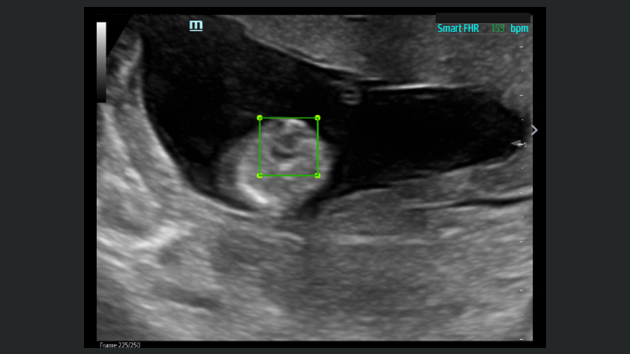

L'├®chographe TE9 a ├®t├® con?u pour faciliter les soins et ├®tendre les capacit├®s d'imagerie pour lŌĆÖanesth├®sie, les urgences et les soins intensifs. Gr?ce ├Ā ses fonctions avanc├®es, son grand ├®cran tactile et sa technologie d'imagerie sup├®rieure, l'├®chographe TE9 permet d'am├®liorer l'efficacit├® clinique et dŌĆÖassurer un diagnostic en toute confiance. Gr?ce ├Ā des outils dŌĆÖacquisition et de calculs automatiques, les soignants peuvent obtenir des mesures rapides et reproductibles dans le cadre d'examens et proc├®dures fiables, m├¬me dans des environnements o├╣ le rythme est soutenu.